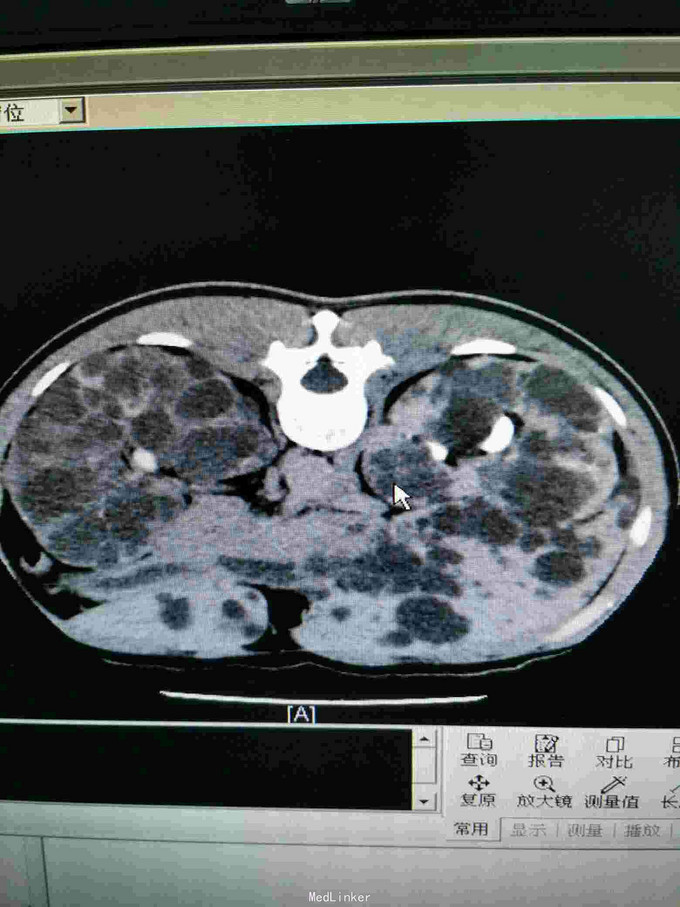

主诉:发现双侧多囊肾3年 病史:患者中年男性,于3年前无明显诱因出现双侧腰部不适,伴肉眼血尿。遂于外院行彩超提示双侧多囊肾伴肾结石,未行特殊处理。3月前再次出现双侧腰部酸痛,伴肉眼血尿,可见血丝,伴尿道烧灼感。无尿频、尿急,无排尿困难,无脓尿。现为进一步诊治收入我科。

查体:左肾区叩击痛(+),右肾区叩击痛(+),余未见异常。 辅查:2015-12-28盆腔CT平扫+增强:双侧多囊肾改变。

诊断:双侧多囊肾 治疗:完善三大常规、生化、凝血等相关检查,评估手术风险,与病人家属及时沟通,择期行手术治疗。同时注意治疗肾结石,保护肾功能。